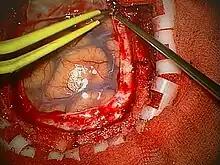

Craniotomia é uma operação cirúrgica em que um retalho ósseo é temporariamente removido do crânio para acessar o cérebro. Craniotomia é uma operação crítica realizada em pacientes que sofrem de lesões cerebrais ou traumatismo cranioencefálico Craniotomia se distingue da craniectomia (em que o retalho ósseo do crânio não é reposto imediatamente, permitindo o cérebro inchar, reduzindo assim a pressão intracraniana) e de trepanação, a criação de um orifício através do crânio para acessar a dura-máter. O tamanho e localização das craniotomias variam de acordo com o objetivo e estrutura a ser abordada. As craniotomias de pacientes vítimas de traumas crânio-encefálico, por exemplo,variam com o tamanho do hematoma a ser drenado e a necessidade de descompressão do tecido cerebral - variam de trepanações únicas para hematomas localizados até as ditas craniotomias descompressivas para tumefações cerebrais difusas.Atualmente, vêm sendo empregadas craniotomias pequenas para algumas lesões profundas (como tumores) e cirurgias de aneurisma cerebral ("Key-hole surgery").Normalmente as pessoas que se submetem a algum tipo de cirurgia invasiva cerebral, por se tratar de uma região com muita vascularização e comprometimento terciário, acaba tendo sequelas, sejam elas de primeira ou segunda ordem.

A craniotomia é realizada a partir da abertura do crânio onde permite o acesso às estruturas abaixo do crânio onde é permitido realizar a retirada de um tumor cerebral ou um coagulo sanguíneo o que resulta na recuperação do tecido cerebral ou de vasos sanguíneos e interrupção de um sangramento intracraniano.